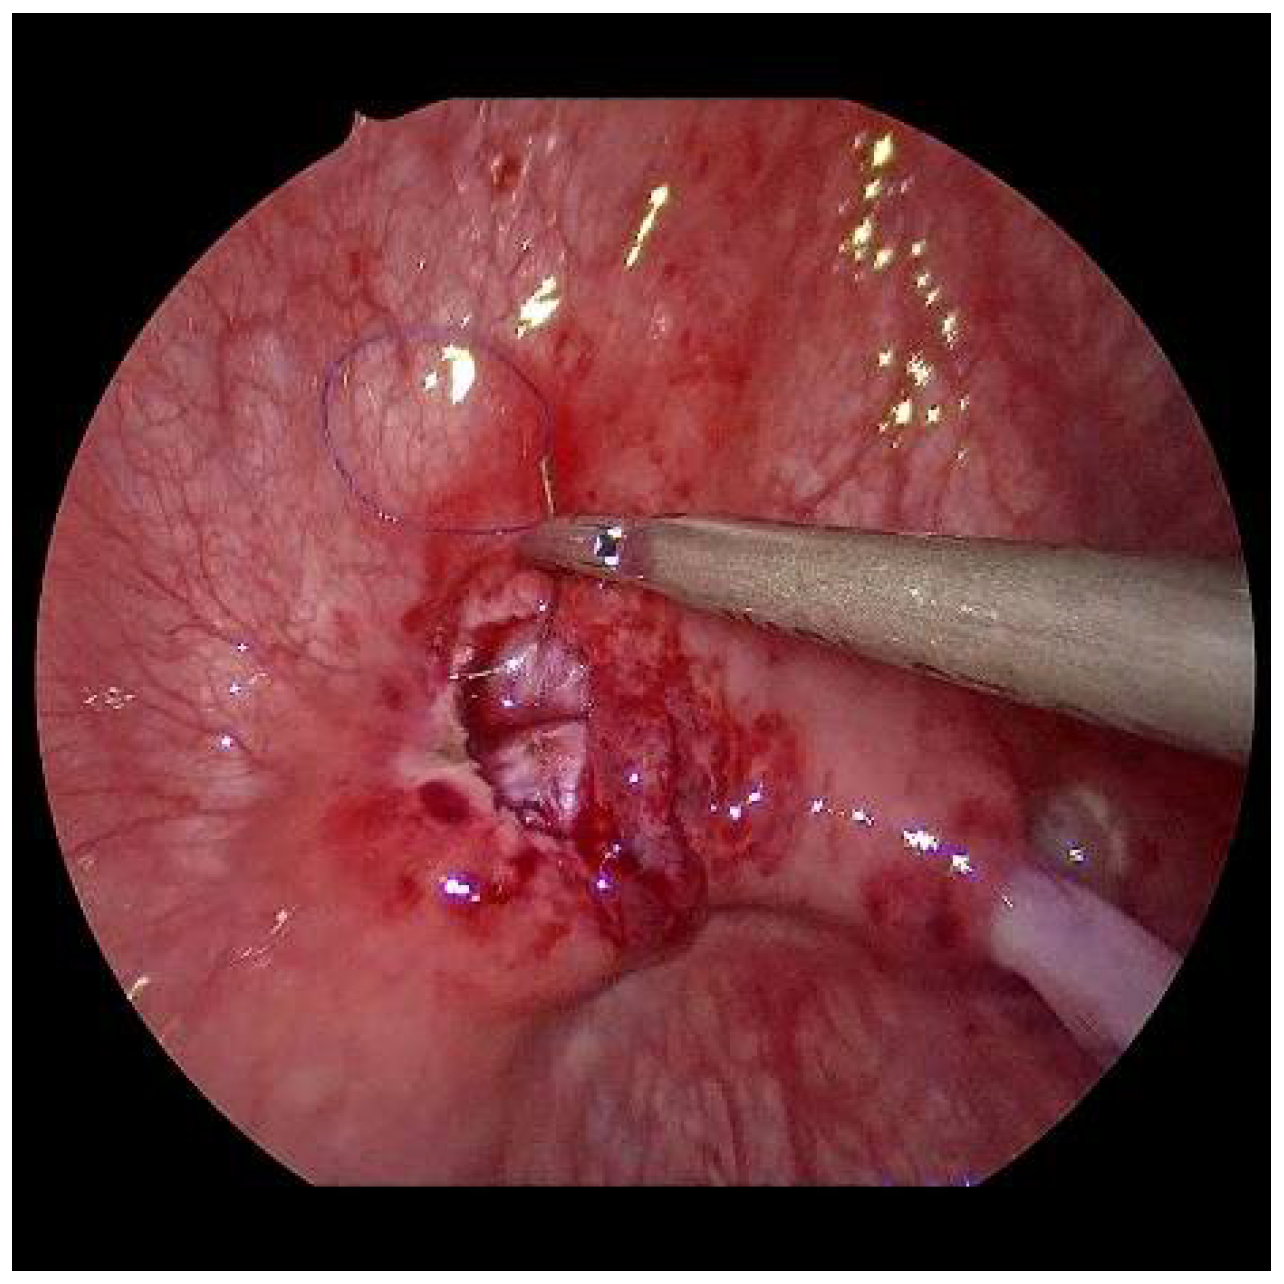

After sparingly shortening and spatulating, the neoostia are created with 5/0 polyglyconate or polyglactin sutures (Figure 7). Depending on the age of the patient, a submucosal ureteral course of 3 to 5 cm in length can thus be achieved. If the finding is unilateral, the original mucosa incision must be closed (Figure 8). Only in exceptional cases, e.g., renal insufficiency, are the ureters splinted for 6 days by percutaneously inserted splints. Finally, the bladder is drained through a balloon catheter for at least 1 to 2 days. After the trocars have been removed, the trocar incisions are only adapted cutaneously, using skin patch strips. The patients are discharged home with problem-free, spontaneous micturition, safe well-being, and regular ultrasound findings.

Figure 8.

Aspect at the end, with closed mucosal defect on the right and the neoostium on the left.